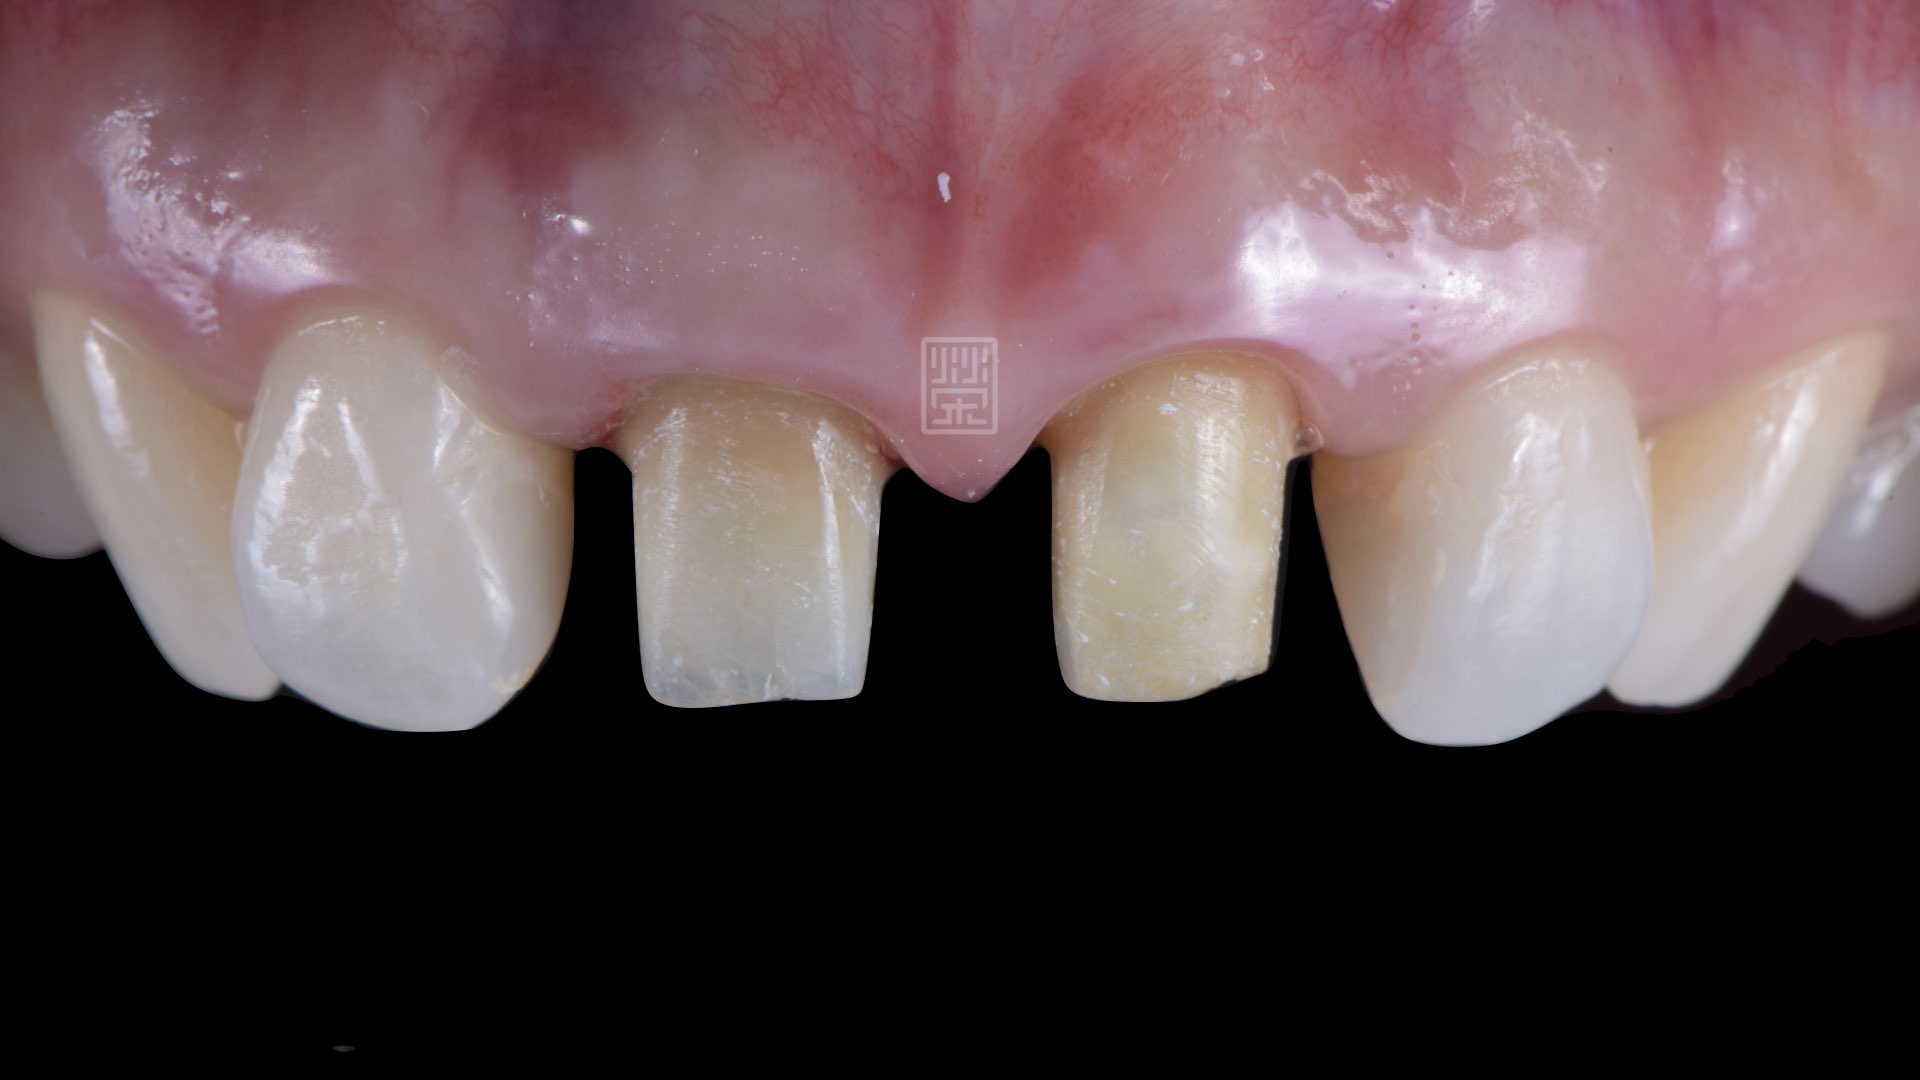

榮醫師診察後,主要是全瓷冠破裂,造成顏色與自然牙不同,但因為全瓷冠邊緣不密貼,長期造成牙齦發炎,所以牙齦有局部萎縮。

全瓷冠變色,牙齦萎縮